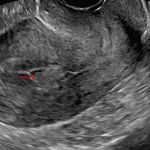

Age: 21

Sex: Female

Indication: Persistent bloody discharge 3 weeks following vaginal delivery

Findings

- Well demarcated echogenic mass in the lower endometrial canal measuring 2.2 x 1.4 x 1 cm with avid Doppler flow extending from the posterior uterine wall into this mass

- Normal appearance of the ovaries

- Trace free fluid in the cul-de-sac

Diagnosis

Retained products of conception

Well demarcated echogenic mass in the lower endometrial canal measuring 2.2 x 1.4 x 1 cm with avid Doppler flow extending from the posterior uterine wall into this mass, which in this patient with recent history of vaginal delivery is concerning for retained products of conception.

Normal appearance of the ovaries.

Trace free fluid in the cul-de-sac.